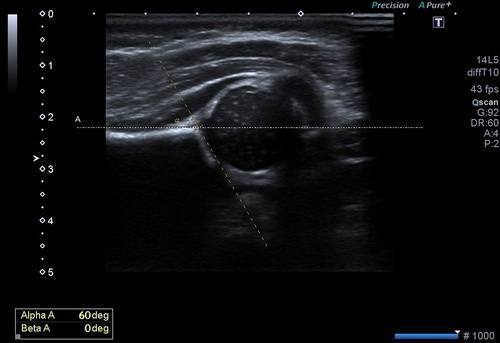

İncelemede parametrik ölçülerden alfa ve beta açısı önemlidir. Alfa açısının 60 derece üzerinde olması kalça gelişiminin genel olarak normal seyrettiğini düşündürür. 60 derecenin altı ise dereceye göre bir sınıflama yapılır ve buna göre takip ve tedavi planlanır.

Şekilde normal kalça eklem gelişimi olan alfa açısı 60 derecenin üzerinde, beta açısı 55 derecenin altında olan bir bebeğin kalça ultrasonu görüntüsü yer alıyor.